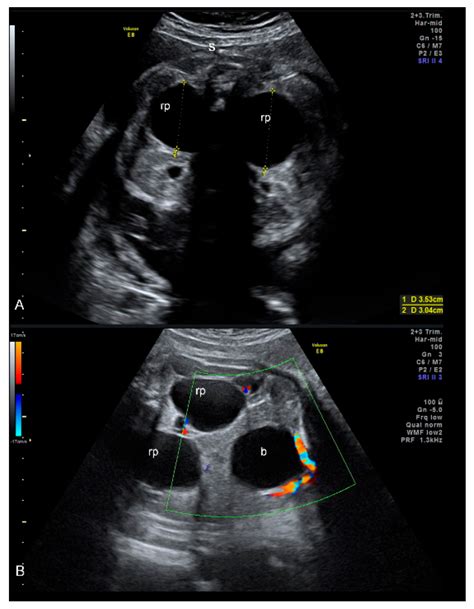

Pyelectasis of the fetus is typically diagnosed during routine prenatal ultrasound examinations. The diagnosis is based on the measurement of the anteroposterior diameter (APD) of the renal pelvis. The severity of pyelectasis is categorized as follows:

Severity APD Measurement (mm)

Mild 4-7

Moderate 7-10

Severe Greater than 10

Pyelectasis of the fetus refers to the enlargement of the renal pelvis, which is the part of the kidney that collects urine before it drains into the ureter. This condition is typically classified based on the severity of the dilation. Mild pyelectasis is often considered a normal variant and may resolve on its own, while moderate to severe pyelectasis may require further evaluation and monitoring.